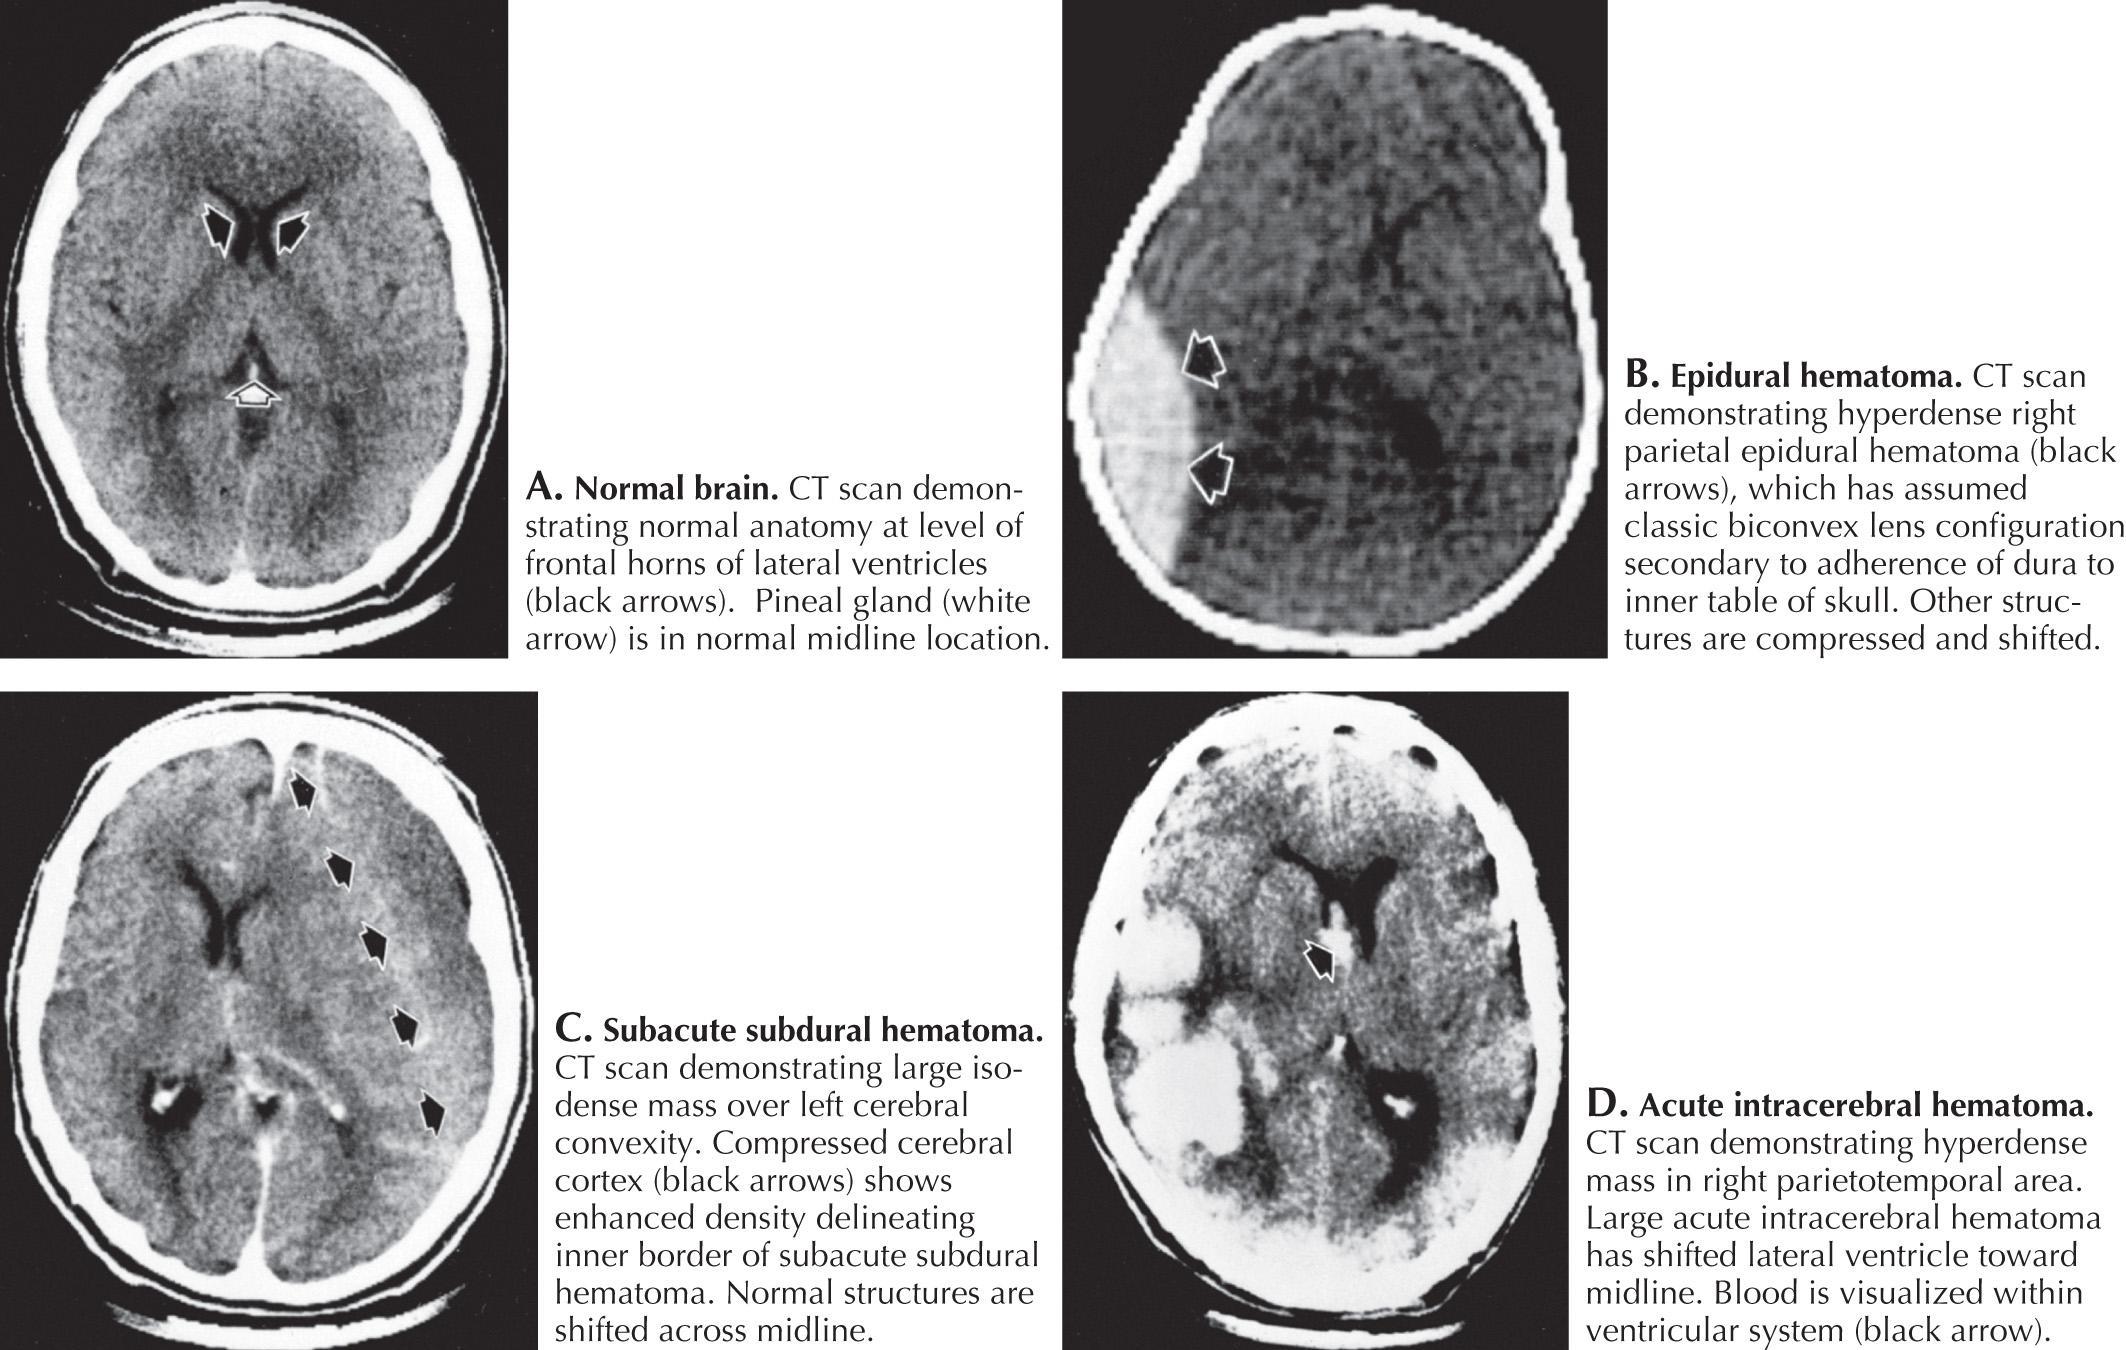

EH represents an acute blood collection contained between the dura and inner table of the skull. These occur in approximately 2% of all TBIs ( Fig. 19.5 ) and 5%–15% of fatal head injuries. EHs most commonly develop in the temporal and parietal regions; 90% of EH are associated with a skull fracture that results in lacerations of vascular structures, more commonly the middle meningeal artery ( Fig. 19.6 ) or, less commonly, venous injuries.

Immediately after the closed head injury, the patient classically experiences an initial but relatively brief loss of consciousness secondary to the primary concussive injury. This is then followed by a “lucid interval” with return of wakefulness, which can be reassuring. Subsequently, as the torn vessels leak and the EH expands, regional brain compression leads to a rapid lapse into coma (see Fig. 19.3 ). This presentation occurs in less than one-third of affected individuals. Most patients do not have a lucid interval. Cranial CT imaging usually demonstrates a hyperdense, biconvex collection between the skull and brain ( Fig. 19.7 ). EHs do not cross cranial suture lines and they expand in thickness under the effect of high pressure arterial bleeding. On occasion, the initial CT is normal. Thus, when the patient is at high risk (i.e., moderate to severe TBI and/or skull fractures) it is essential to closely observe the patient's neurologic exam and level of consciousness and to repeat the CT scan at the slightest clinical change. Once the EH is identified, emergency surgical evacuation is indicated. EHs are one of the most serious sequelae of brain trauma and can be fatal without immediate recognition and surgical evacuation.

Fig. 19.7, CT and Angiogram of Intracranial Hemorrhage.